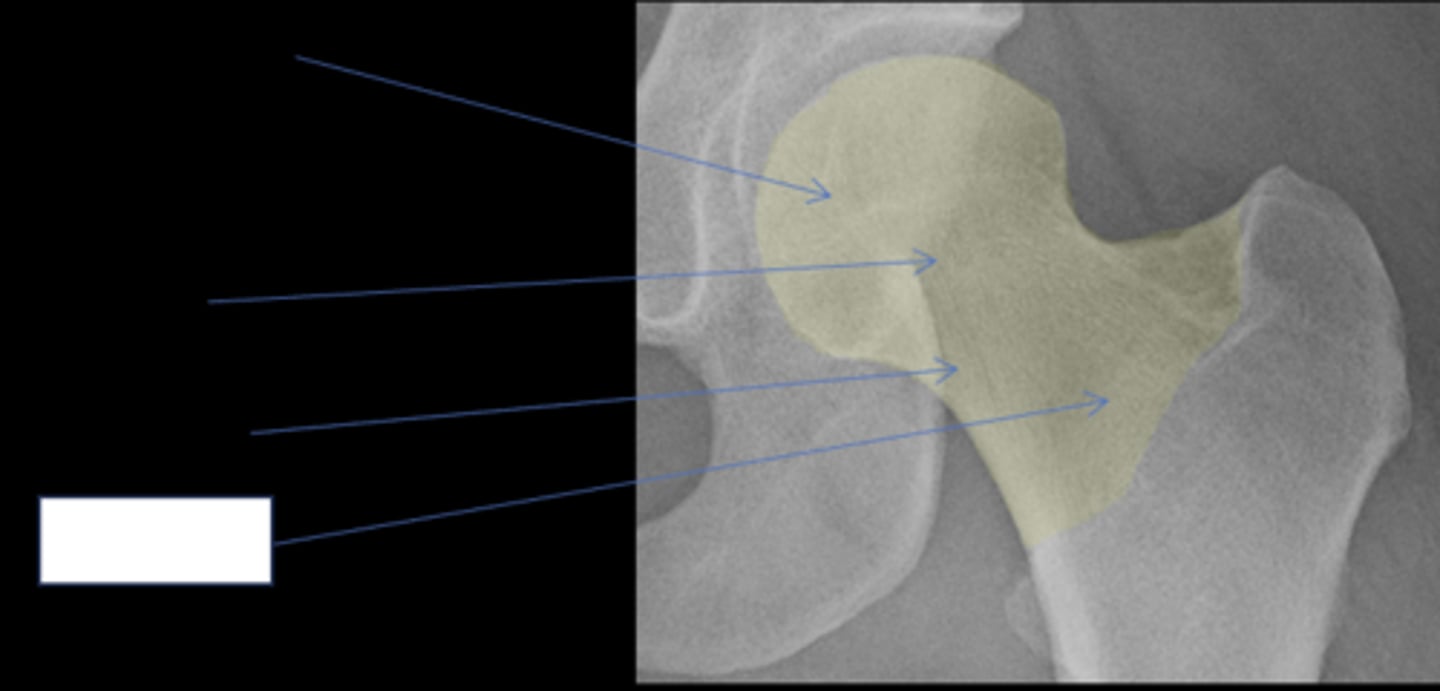

Pubic symphysis

ID 1

<p>ID 1</p>

Left femoroacetabular joint

ID 2 (joint)

<p>ID 2 (joint)</p>

Left posterior sacroiliac joint

ID 3 (joint)

<p>ID 3 (joint)</p>

Left anterior sacroiliac joint

ID 4 (joint)

<p>ID 4 (joint)</p>

9

New cards

Right: gluteus medius

Left: gluteal fat stripe

ID 5

<p>ID 5</p>